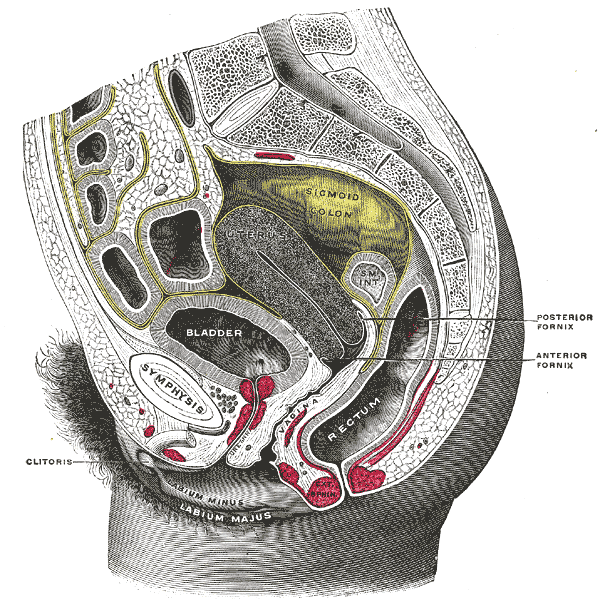

Gross Anatomical Location of the Uterus in the Pelvic Cavity UterusInPelvicCav.gif